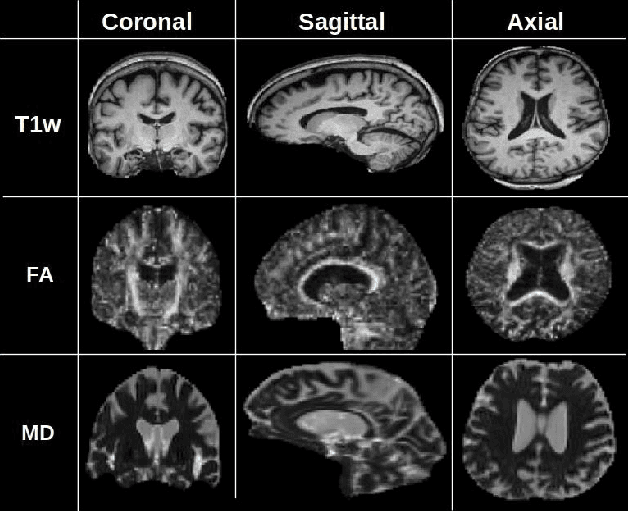

Abstract:Alzheimer's disease (AD) is a progressive brain disorder that causes memory and functional impairments. The advances in machine learning and publicly available medical datasets initiated multiple studies in AD diagnosis. In this work, we utilize a multi-modal deep learning approach in classifying normal cognition, mild cognitive impairment and AD classes on the basis of structural MRI and diffusion tensor imaging (DTI) scans from the OASIS-3 dataset. In addition to a conventional multi-modal network, we also present an input agnostic architecture that allows diagnosis with either sMRI or DTI scan, which distinguishes our method from previous multi-modal machine learning-based methods. The results show that the input agnostic model achieves 0.96 accuracy when both structural MRI and DTI scans are provided as inputs.